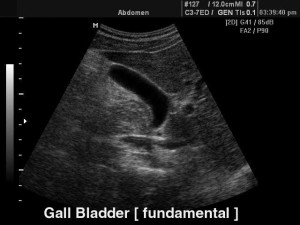

УЗИ желчного пузыря

Главный метод, с помощью которого осуществляется диагностика перегиба желчного пузыря – ультразвуковое исследование (синонимы – эхография, сонография). УЗИ дает возможность не только определить функциональное состояние органа и точную локализацию патологии, но и обследовать его стенки, зоны шейки и протока.

Как отмечают специалисты, выяснить причины перегиба желчного пузыря при его УЗ-исследовании не так просто. Чтобы определить характер патологии (врожденный или приобретенный), УЗИ сначала делается до, а затем после приема яичных желтков, вызывающих повышенную секрецию желчи. Когда перегиб желчного пузыря врожденный, то деформация органа остается без изменений.

Эхопризнаки перегиба желчного пузыря (или эхографические симптомы) при продольном и поперечном сканировании органа на аппарате линейного типа выражаются в том, что на изображении четко просматривается изменение нормальной формы органа в виде эхопозитивных линейных образований различной локализации. Чаще всего перегиб фиксируется в месте перехода тела пузыря в шейку. При этом желчь, находящаяся в пузыре, имеет вид эхонегативного образования.

Кроме того, в ходе исследования моторики желчного пузыря выясняется наличие и степень дискинезии желчевыводящих путей, которая бывает в 80% случаев диагностики перегиба желчного пузыря.